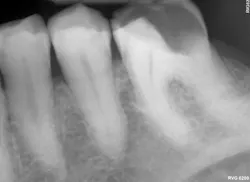

The viscosity of Activa BioActive Bulk Flow is ideal for various clinical situations. For example, in cases requiring restoration of deep boxes and cavernous lesions, the material ensures proper treatment thanks to its flowability and dual-cure properties. With its unlimited depth of cure and no layering/capping requirement, dentists can be confident that the risk of voids is minimized.

Furthermore, Activa BioActive Bulk Flow provides an option for dentists who appreciate Activa’s bioactive properties but want to work without a dispenser. Activa BioActive Bulk Flow simplifies inventory thanks to ShadeFusion universal color matching. The material is sufficiently radiopaque so dentists can be confident that it will be visible for any clinician evaluating their patient for years to come.